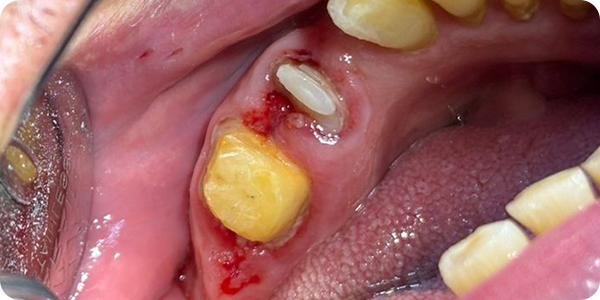

2. Validación (Prueba de resina):

Se solicitó una prueba de resina para asegurar el ajuste marginal exacto antes de proceder al fresado final en zirconia, garantizando que el tejido blando se mantuviera estable.

Se identificó riesgo de adaptación y posible fractura por la vía de inserción desfavorable. Para mitigar esto, se optó por una validación mediante prueba de resina para asegurar el sellado marginal antes del fresado definitivo.

- Gestión de Expectativas: A pesar de los riesgos técnicos de fractura por inserción detectados en el CAD, la validación con prototipos de resina permitió ajustar los parámetros de fricción para un asentamiento pasivo.

- Prototipado en resina: La lección más valiosa fue la confirmación de que, en encías comprometidas, la prueba de resina es el "seguro de vida" de la restauración final.